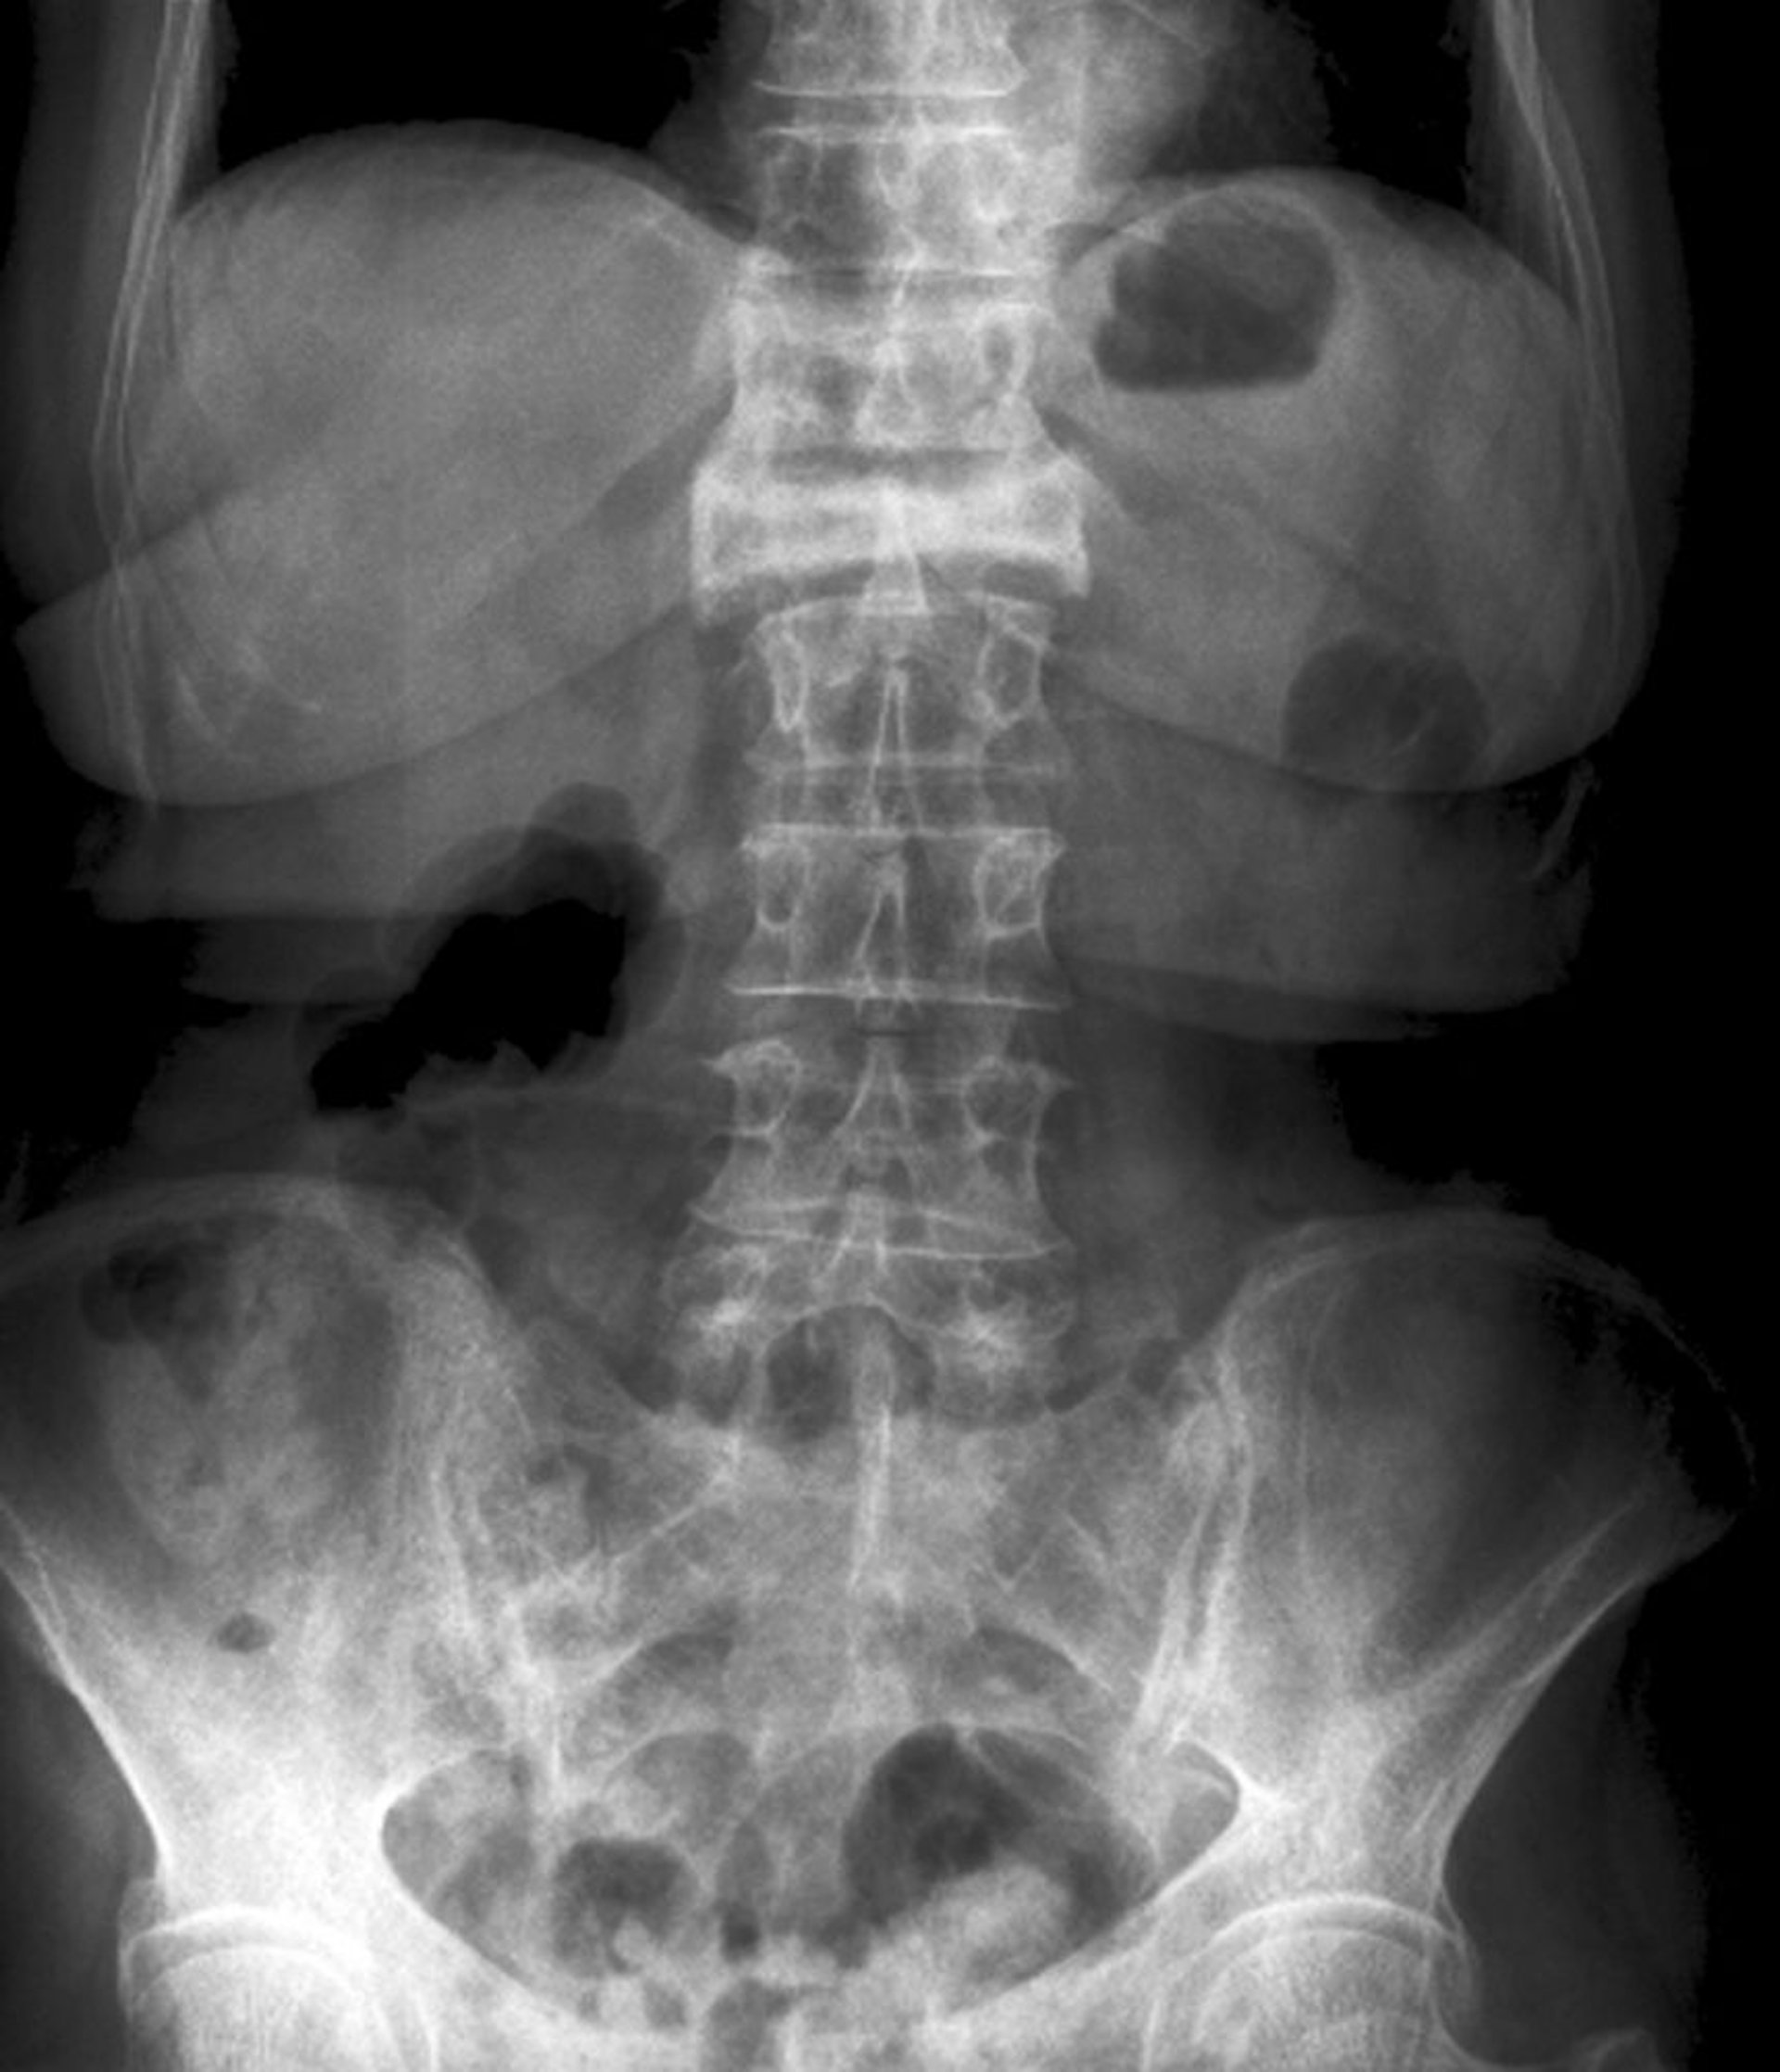

Incidence de face d'une fracture par compression (tassement) sévère

Cette fracture par compression (tassement) de la 1ère vertèbre lombaire est visible en incidence de face sous la forme d'une perte sévère de hauteur et d'une augmentation de la radiodensité.